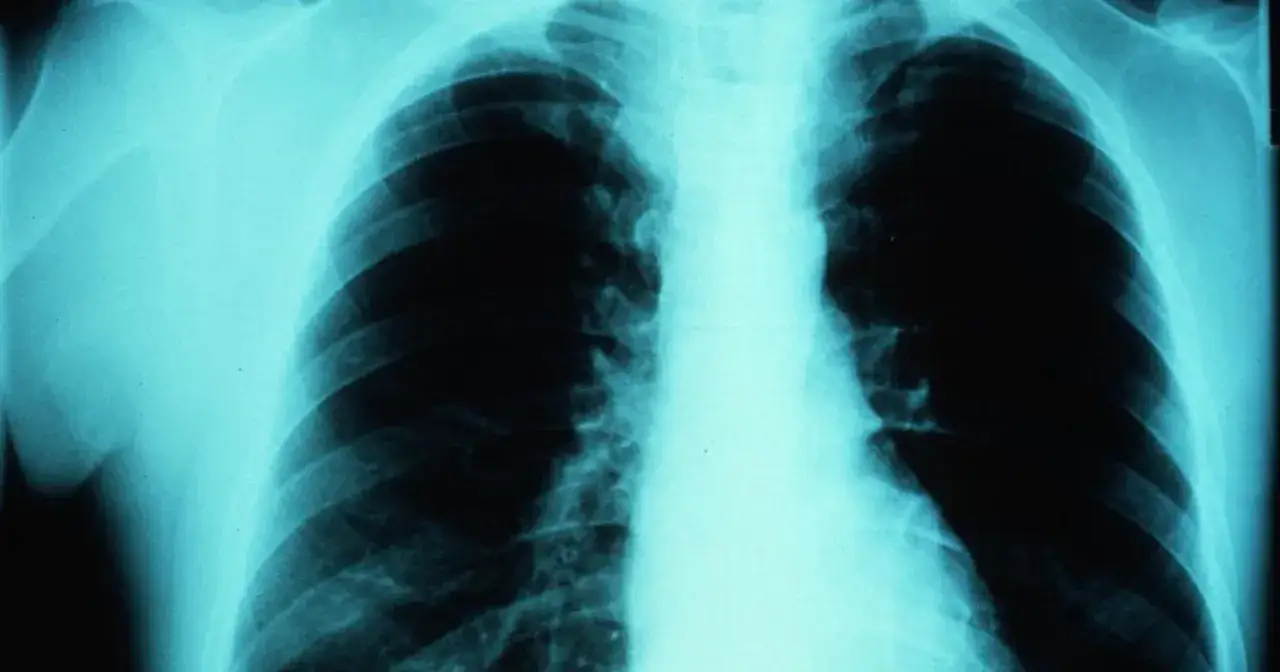

Diagnostyka, która widzi więcej: zajrzyj do wnętrza ciała bez skalpela

Techniki diagnostyki obrazowej wykorzystujące izotopy to prawdziwe okno na wnętrze ludzkiego organizmu. Pozwalają one na nieinwazyjne badanie procesów metabolicznych, przepływu krwi czy funkcjonowania narządów, co jest nieosiągalne dla tradycyjnych metod, takich jak rentgen czy USG. Dzięki temu lekarze mogą postawić trafne diagnozy na wczesnym etapie choroby.